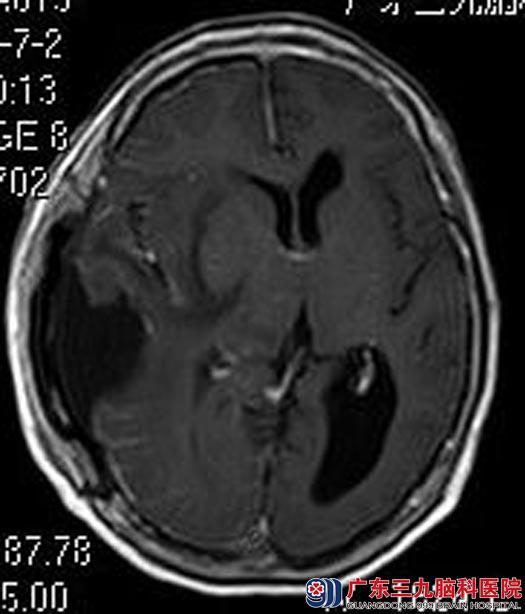

由鲁明主任主刀,在全麻下行右侧颞顶部占位病变切除术,术前导航计划,术中根据术前导航定位,在显微镜下予以肿瘤全切。术后病理结果:脑膜瘤,WHO I,考虑微囊型。

▲手术后